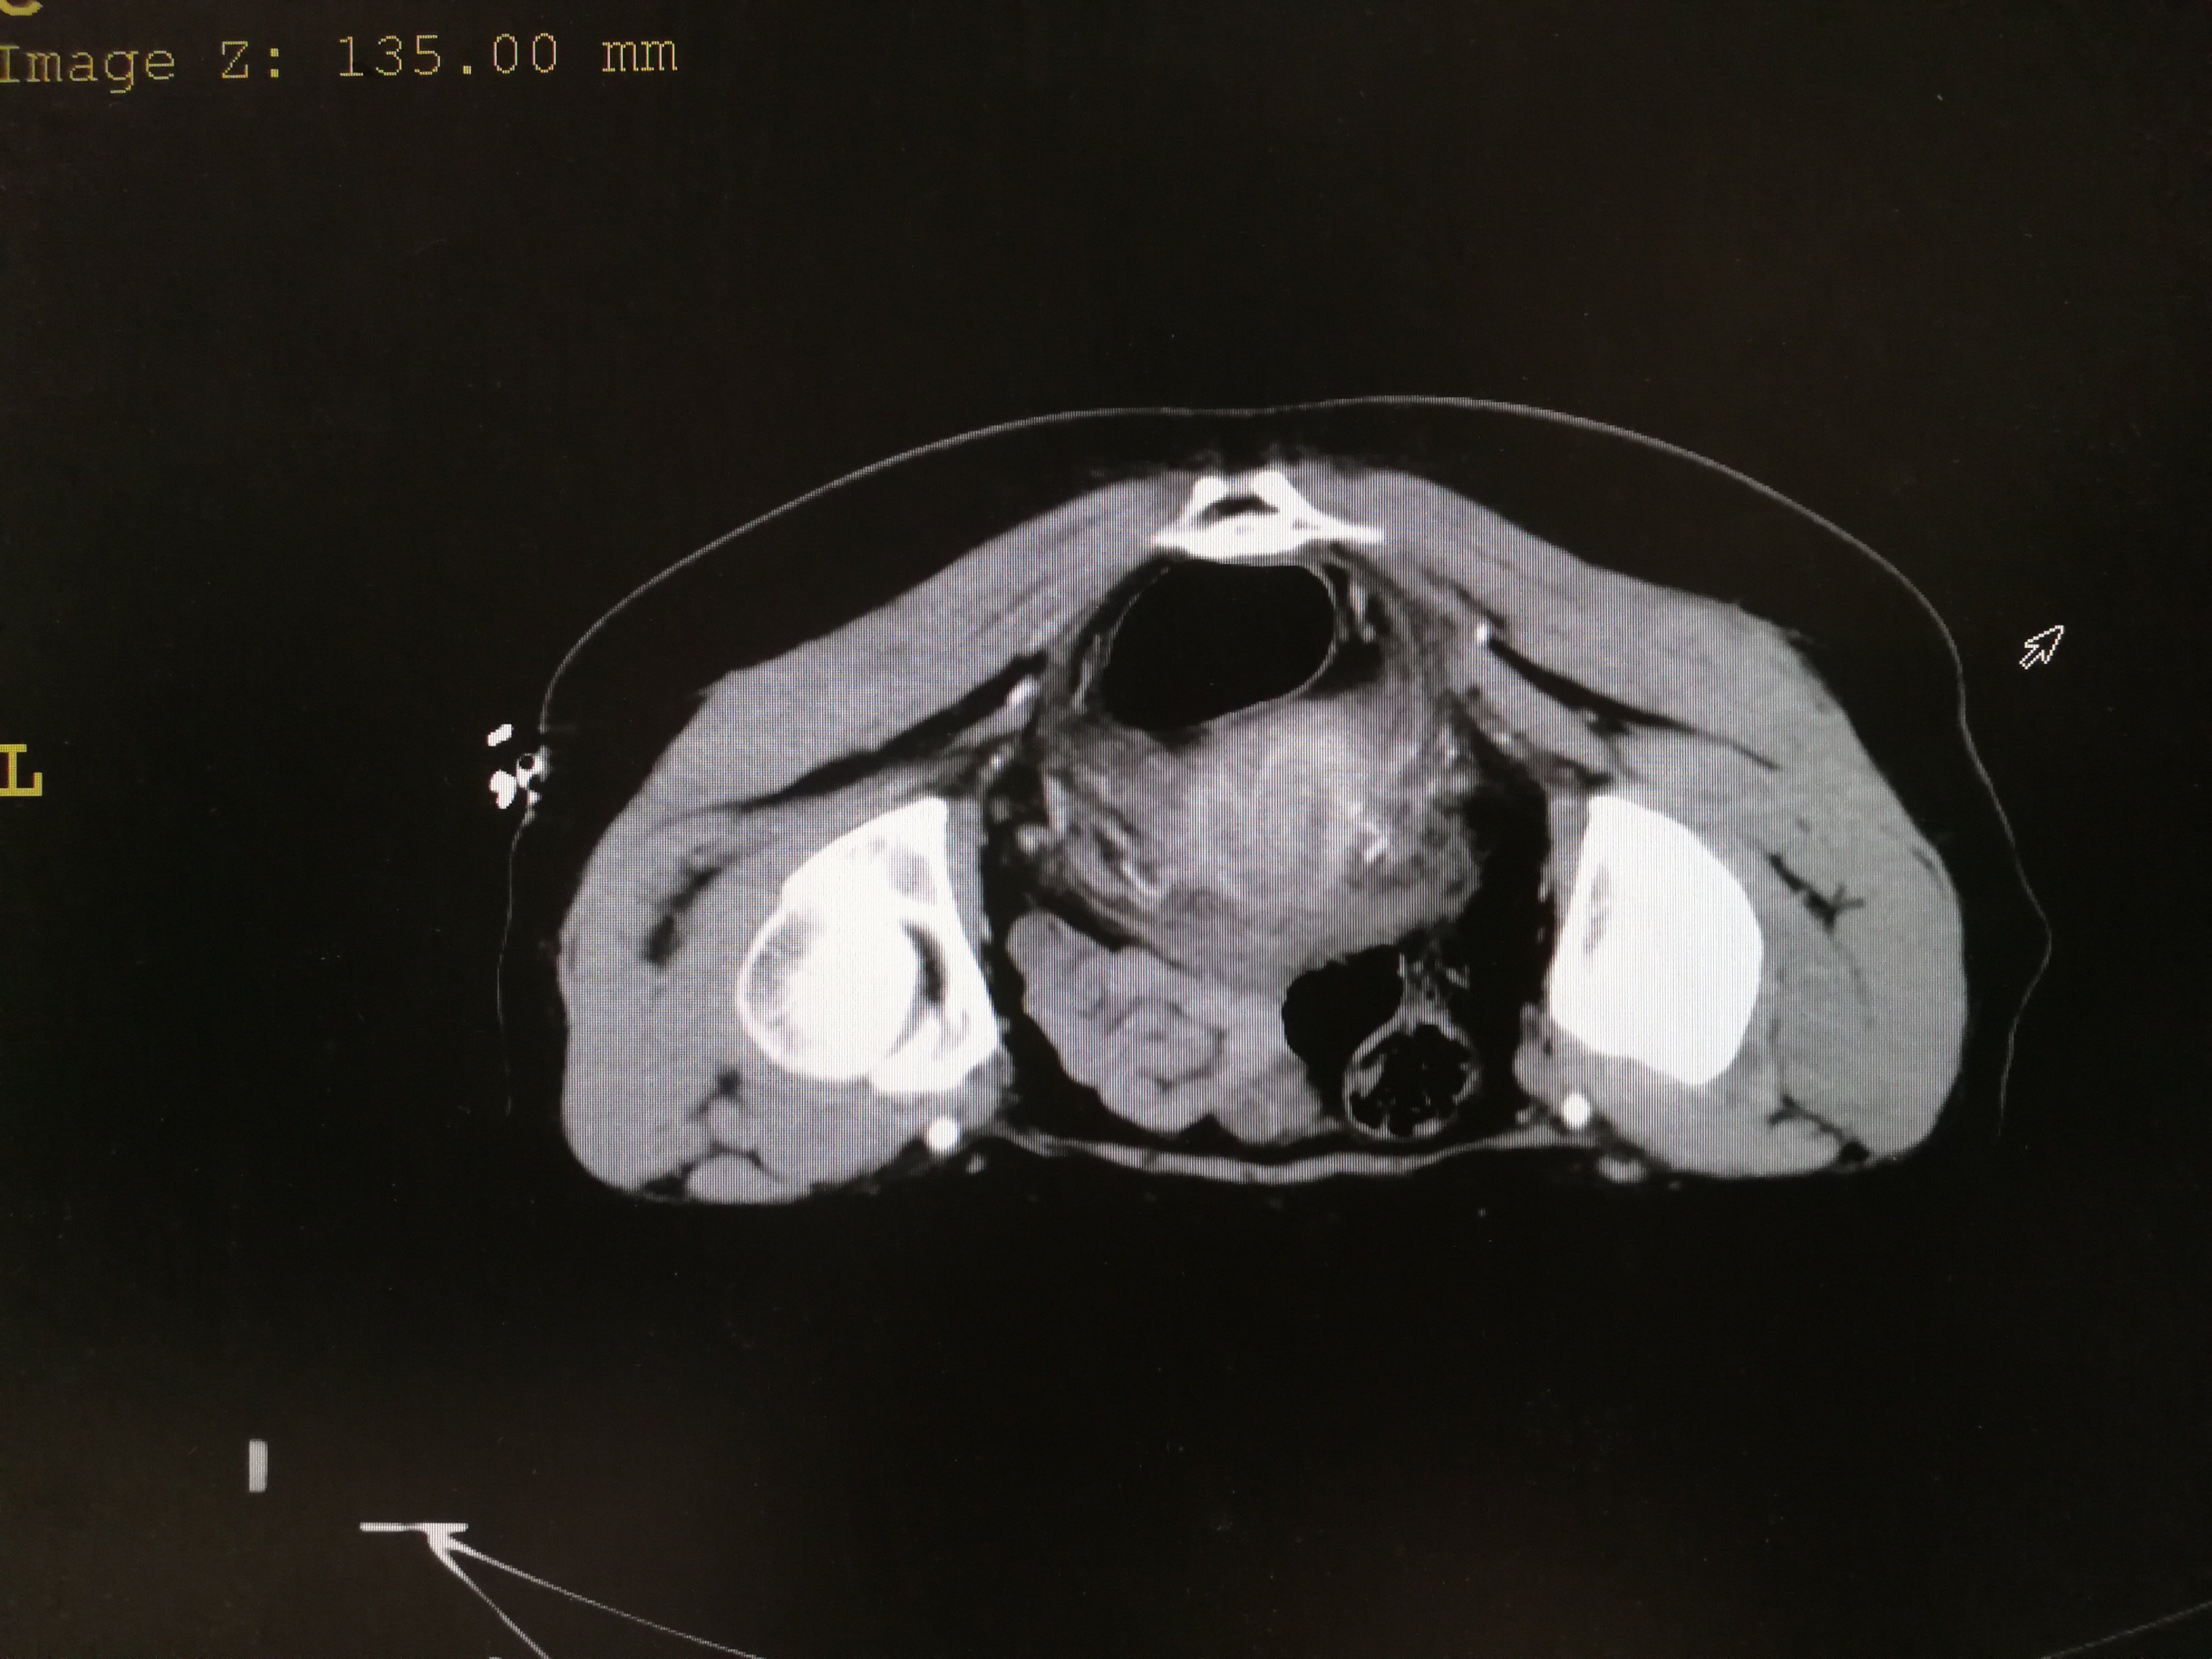

肿瘤科精神心理科妇产科 展开全部 卵巢这个占位是畸胎瘤的可能较大